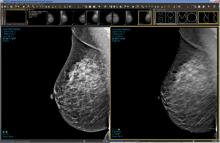

AI is also helping simplify complex tasks and help reduce the reading time on involved exams. One example of this is in 3-D breast tomosythesis with hundreds of images, which is rapidly replacing 2-D mammography, which only produces 4 images. Another example is automated image reconstruction algorithms to significantly reduce manual work. AI also is now being integrated directly into several vendors' imaging systems to speed workflow and improve image quality.